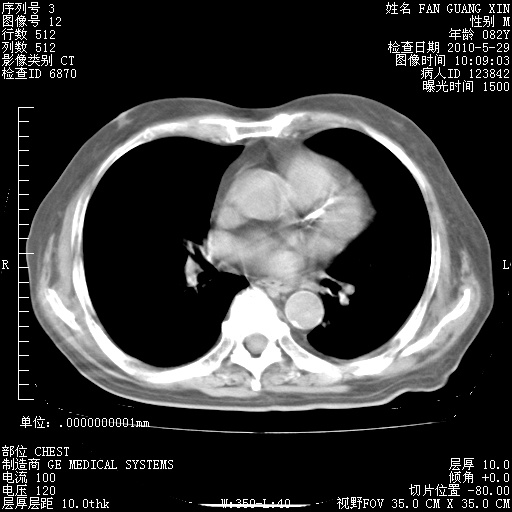

再治疗10天后的肺部CT

再治疗10天后的肺部CT 纵膈窗